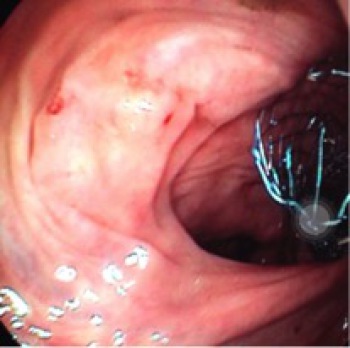

La endoscopia es una técnica que utiliza los orificios naturales del organismo, la boca y el ano, para realizar exploraciones en principio con fines diagnósticos. Sin embargo, poco a poco su uso avanza para realizar el tratamiento de determinados procesos. Se trata de “operar por dentro” sin abrir.

La colocación de prótesis en el tubo digestivo por vía endoscópica en caso de obstrucción puede evitar la intervención quirúrgica. Las indicaciones más habituales para la colocación de prótesis son el cierre de fístulas y la estenosis (estrechamiento) debido a tumores malignos o estenosis benignas postquirúrgicas o por cicatrices inflamadas (como en el caso de la enfermedad de Crohn). En los últimos años también se está extendiendo el uso de prótesis para el drenaje de colecciones (como pseudoquistes pancreáticos tras pancreatitis aguda) guiada por Eco-endoscopia (endoscopio especial con la capacidad de poder realizar una ecografía desde dentro del tubo digestivo)En el caso de los tumores malignos, la técnica no persigue curar sino aliviar los síntomas del paciente y mejorar su calidad de vida. En las estenosis benignas, la colocación de la prótesis sí puede solucionar el problema. Las ubicaciones más frecuentes donde se colocan suelen ser el esófago, el colon y la vía biliar, aunque también se ponen en el duodeno, el estómago y la vía pancreática.

Las prótesis, que son pequeños tubos que permiten abrir la zona obstruida, pueden ser de metal o de plástico. Existen diversos modelos, las constituidas de ligas metálicas como Elgiloy (cobalto y cromo), Nitinol (niquel y titanio) y acero inoxidable, disponibles en varios tamaños, formas, revestidas o no. Las prótesis van montadas en un catéter (tubo fino) y sujetas con un hilo, y el principio de la colocación se basa en la transposición de la obstrucción a través de una guía, sobre la cual será pasado el sistema de introducción con la prótesis en la forma restringida. Posterior a la ubicación adecuada abarcando toda la estenosis, se libera la prótesis permitiendo su expansión y posteriormente el sistema introductor es retirado.

El proceso se realiza bajo control endoscópico y radiológico y con el paciente bajo sedación profunda.